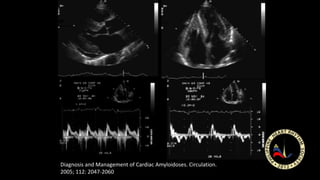

Diagnosis and Management of Cardiac Amyloidoses. Circulation.

2005; 112: 2047-2060